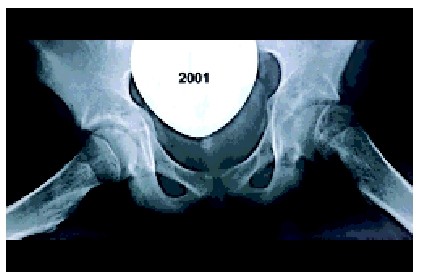

Thomas Mertens, een 15-jarige zwakbegaafde jongen, komt in 1995 op het spreekuur van de polikliniek. In 1993 is bij hem ECF rechts gediagnosticeerd. Thomas is een maand voor zijn bezoek aan de poli gevallen en heeft toen de eerste hulp bezocht, waar geen afwijkingen werden gevonden. De huisarts verwees hem daarop naar de fysiotherapeut. Ondanks therapie bleef hij pijnklachten van de knie en heup houden. Tijdens het spreekuur orthopedie worden foto's van de linker heup gemaakt waarop een ernstige epifysiolyse met een volledig afgegleden femurkop is te zien. Onder narcose wordt nog dezelfde dag geprobeerd onbloedig te reponeren. Omdat dit niet het gewenste resultaat oplevert, wordt hij behandeld met een correctie-osteotomie. Een halfjaar na de operatie is de heup stijf in 40° flexie en 10° exorotatie. Op de röntgenfoto lijken de osteotomie en de groeischijf geconsolideerd. De stijve heup kan passen bij een beginnende chondrolyse of kopnecrose. Anderhalf jaar later is op de röntgenfoto nog een vage gewrichtsspleet zichtbaar. Ondanks de functionele stand van de pijnloze, stijve heup zal Thomas ernstig lichamelijk gehandicapt blijven.